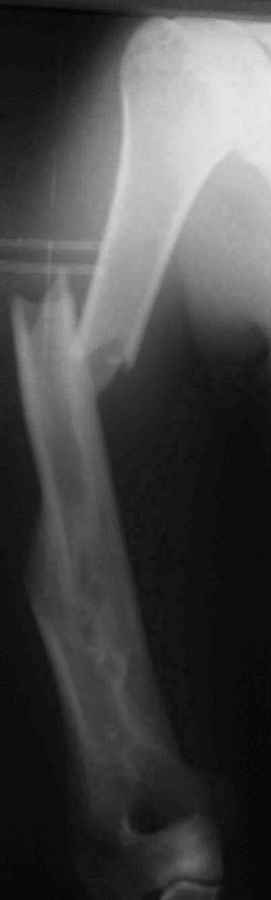

Результат консервативного лечения короткого косого перелома диафиза плеча врачами общей практики в условиях развивающейся страны у больного low social class

Предыдущий перелом плеча – пару лет назад ДТП. К сожалению, этот крайне важный жизненный опыт не изменил стиль вождения больногоПоследний перелом плеча – ДТП 2 мес назад. В связи с дефицитом как специалистов – ортопедов, так и операционного времени в принципе больной был осмотрен в приемном покое врачом общей практики, наложена U-образная гипсовая повязка и отправлен домой. Я впервые увидел больного через 6 нед после травмы, сделал снимки и снял повязку. Фотографии больного - 2 мес после травмы. снимки - при травме и через 6 недель

Вывод: Если плечо не трогать, оно нормально срастается.

Тот же самый вывод наукообразно: данное клиническое наблюдение свидетельствует, что консервативное лечение переломов диафиза плеча является патофизиологически оптимальным, приводит к удовлетворительному функциональному результату и явлеяется наиболее экономически щадящим как для больного, так и для системы государственного здравоохранения в целом.